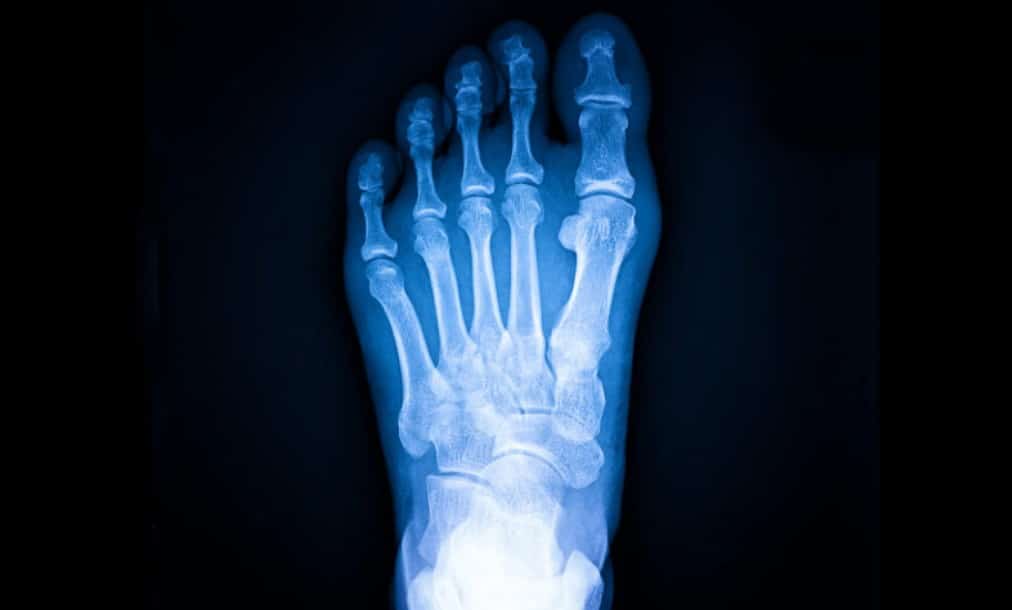

La mayoría se producen en huesos de las piernas y pies, como la tibia o los metatarsianos, ya que soportan gran parte del impacto en actividades físicas intensas.

Dependiendo de los hallazgos, el especialista puede sugerir estudios complementarios como radiografías —que en etapas tempranas no siempre muestran la lesión—, resonancia magnética o gammagrafía ósea, con el fin de confirmar el diagnóstico y precisar la extensión del daño.